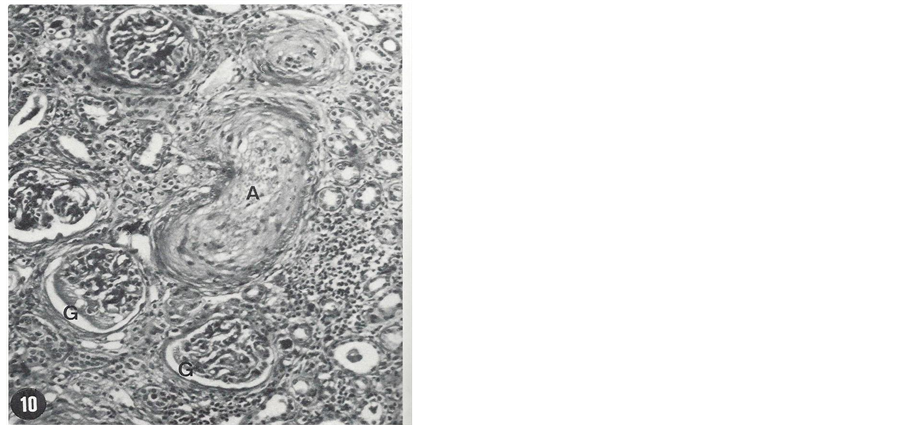

A patient is presented here to exemplify the devastating effect of uncontrolled hypertension. A 25-year-old African American male has had numerous hospital admissions in Oklahoma City, Oklahoma, USA for investigation and treatment of hypertension. He presented to a medical clinic for the first time with complaint of severe headache for four days duration in November 1972. Physical examination showed blood pressure (BP) 240/140 mmHg (stage 4 hypertension) and grade 2 (K-W-B) retinopathy. BUN and serum creatinine (ScR) were 27 mg/ dl and 2.3 mg/dL, respectively. A complete work-up for secondary hypertension including renal artery stenosis was negative. A wedge biopsy of one of the kidneys during exploratory laparotomy was obtained and studied using light microscopy (LM), immunofluorescence microscopy (IFM) and transmission electron microscopy (TEM). LM was unremarkable except for slight arteriolar thickening. IFM was negative. TEM study of an arteriole showed necrosis and hyperplasia of smooth muscle cells, small amount of collagen tissue and electron- dense deposits. These changes indicated early stage of severe vascular changes in the kidneys. He was treated with antihypertensive therapy; his BP was reduced, headache was aborted and kidney function was improved. However, he was noncompliant and not regularly taking his prescribed BP medication. Thus during routine clinic visits, his BP had always been elevated in excess of 240/140 mmHg. After 36 months he developed sudden onset of exertional dyspnea, paroxysmal nocturnal dyspnea and oliguria and was admitted into a hospital with a diagnosis of CHF. His BP was in the range of 250 - 260/140 - 150 mmHg and flame shaped hemorrhages were noted on ophthalmoscopic examination giving rise to the clinical diagnosis of malignant hypertension. His renal function was markedly decreased with BUN and Scr levels of 110 mg/dL and 11.5 mg/dL, respectively. Conservative management failed to control BP and CHF; hence he was placed on maintenance hemodialysis. Despite hemodialysis and antihypertensive therapy, his BP remained elevated. Finally in order to reduce BP, he underwent bilateral nephrectomy, after which BP could be reduced with antihypertensive therapy. He didn’t develop stroke. Kidney pathology consisted of necrotizing arteriolitis and occlusive changes which were consistent with clinical diagnosis of malignant hypertension. LM histopathology of the nephrectomy specimen is shown in Figure 1 and Figure 2.

Figure 1. Necrosis of a small artery (A), necrosis of parts of two glomeruli (G), a few atrophic tubules and marked infiltration of the intestitium by monomorphic round cells are seen (H & E, 120×). From the nephrectomy specimen.